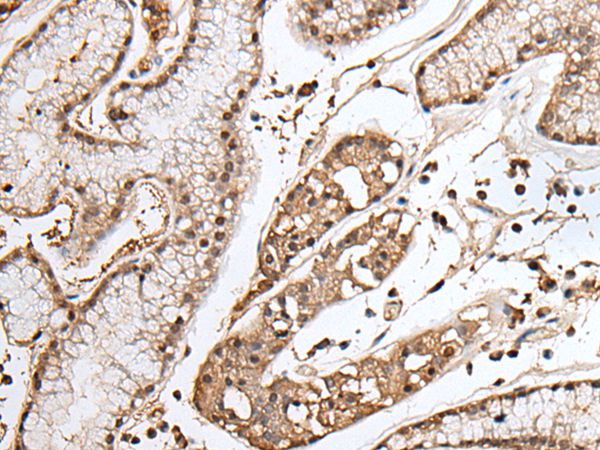

分类: 科研抗体货号: P43470别名: WEE1A; WEE1hu应用: WB,IHC反应种属: Human,Mouse,Rat